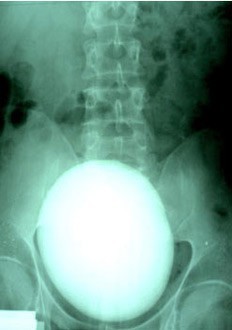

Sarkadi'nin filmleri çekildiğinde doktorlar da gözlerine inanamadı. Adamın böbreğindeki taş tam 17 santimetre büyüklüğündeydi. Yani bir golf topu kadardı...

Adam taşı doğal yollarla düşüremeyeceği için ameliyatla alındı.